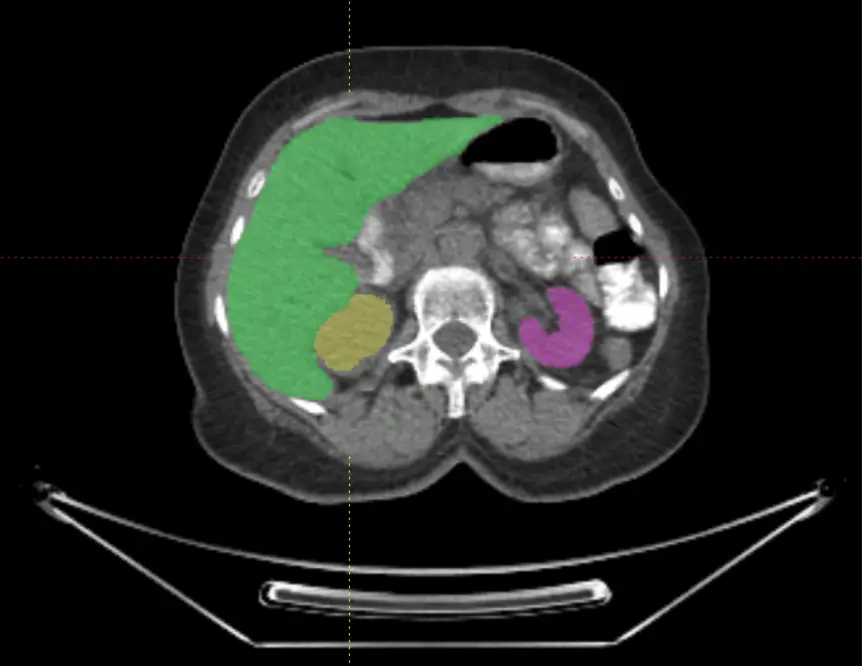

Voiant Hub 2.0 is designed to meet the evolving demands of oncology trials by leveraging AI into key aspects of the imaging workflow. These enhanced capabilities not only improve the reliability of response assessments but also drive earlier insights into tumor biology through imaging biomarkers. As a result, sponsors can make more confident treatment decisions, adapt trial strategies in real time, and ultimately bring therapies to patients faster.

Voiant Hub 2.0 streamlines segmentation and tracking for semi-automated RECIST and volumetric automated RANO assessments, enhancing accuracy, consistency, and compliance in tumor response and tumor burden evaluation.

Powered by Voiant Hub 2.0, our platform captures early biological signals and enables advanced, volumetric tumor characterization—unlocking a growing portfolio of imaging biomarkers that refine trial eligibility, accelerate exploratory endpoints, and drive targeted, image-informed strategies: